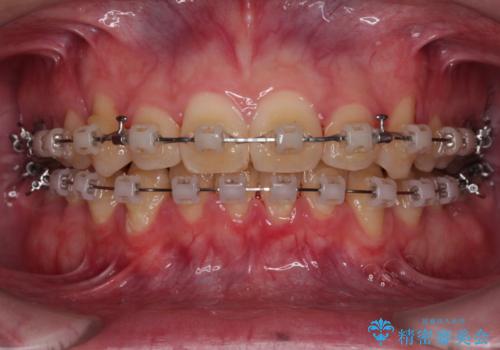

上顎前歯のデコボコを改善してスッキリした口元に ワイヤー装置での非抜歯矯正

- クリアブラケット

上下前歯にデコボコがありましたが、特に上顎の叢生が強く、通常に歯列を整えると、上顎が前方に突出し、口元の突出感が残った仕上がりとなる可能性が考えられました。

補助装置を用いて上顎歯列全体を後方に移動させる力をかけ、唇が閉じやすいような仕上がりを目指して、ワイヤー装置にて矯正治療を行うこととしました。

非常に咬合力が強く、左側の臼歯がなかなか後方へ移動できなかったのですが、2年ほどかけて大変満足のいく仕上がりを達成することができました。